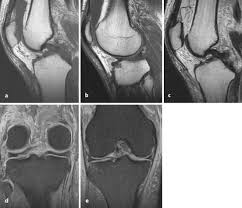

Tractus iliotibialis syndrom mrt. Die Schmerzen am Oberschenkel außen entstehen plötzlich wenn diese Gesäß- undoder Hüftmuskeln schon länger verspannt sind und man dann abrupt an den ständig angespannten Muskeln bzw. Hier handelt es sich um ein Schmerzsyndrom das vor allem bei Läufern auftritt und daher auch als Läuferknie bezeichnet wird. The iliotibial band ITB is a thick band of fascia formed proximally at the hip by the fascia of the gluteus maximus gluteus medius and tensor fasciae latae muscles.

Das Tractus iliotibilais-Syndrom wird auch Läuferknie genannt da es bei Läufern häufiger auftritt. The superficial layer is the main tendinous component and inserts onto Gerdys tubercle on the anterior lateral tibia. Schmerzen können hierbei im gesamten Verlauf vorkommen.

Der Tractus iliotibialis ist ein Faszienstreifen Faszie Binde breitausgedehnte sehnenartige Hülle auf Muskeln der an der Außenseite des. The deep layer inserts on the intermuscular septum of the. Die Sehne die in der Fachsprache Tractus iliotibialis heißt spielt eine Rolle in der Stabilisation des Kniegelenks der Aufrichtung des Beines und.